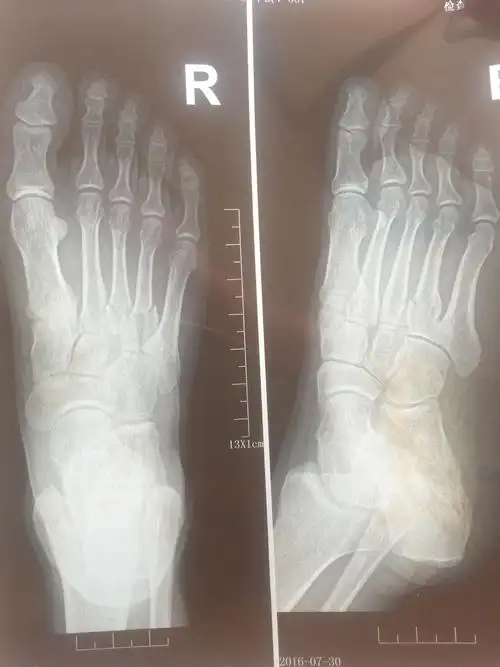

x 射线,脚,骨

脚掌骨折拆石膏后多久可以正常行走 2010-08-18 为什麽骨折的人石膏拿

第一跖趾关节也就是足大拇指与脚掌的第一跖骨形成的关节,为了方便筋

足骨骨折多久能好